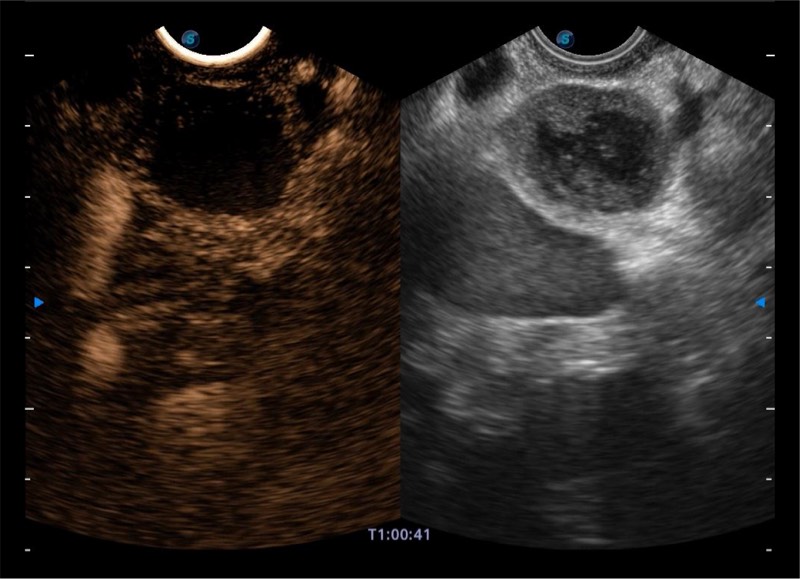

搭载百万级CMOS成像技术

及自主研发凸阵换能器,

可呈现优质的内镜和超声画面

基于二十年的超声技术积累,亚星官网提供了最新一代的独立超声主机,在提供高质量图像的同时满足多学科使用。具备常见多普勒技术并提供弹性成像、声学造影等高端影像技术。新一代传感器具有更强的抗干扰能力并减少图像伪影。

4-12MHZ宽频输出